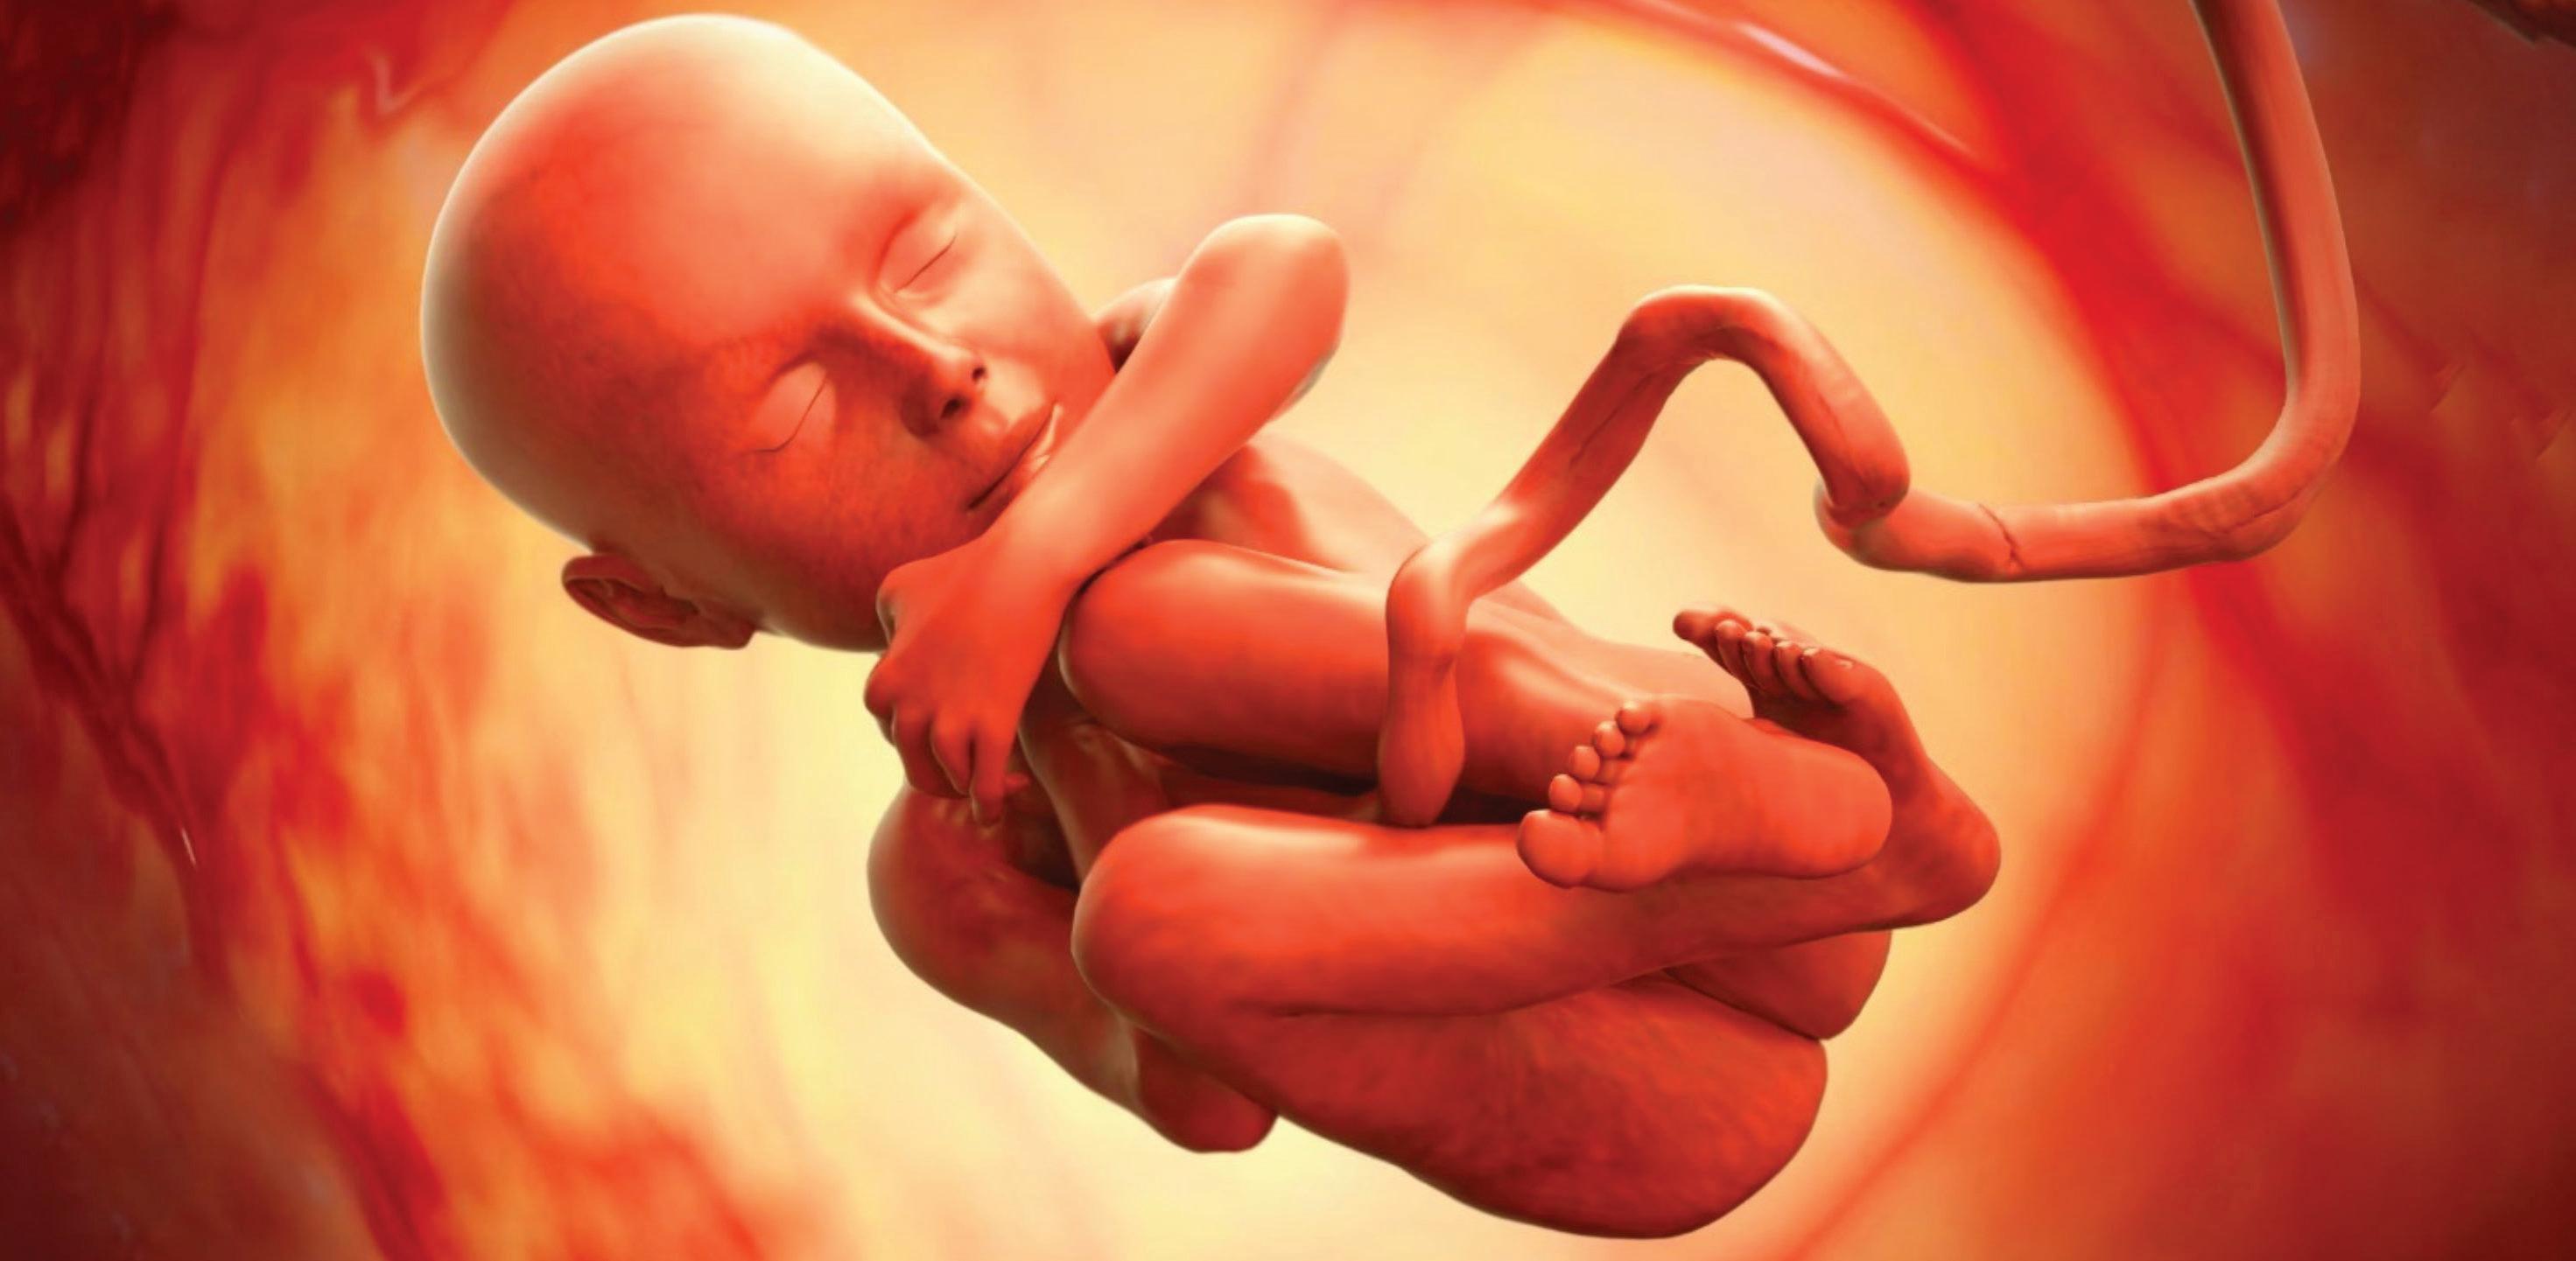

The first trimester— spanning from conception to 13+6 weeks—is no longer considered a “blind phase” of pregnancy. With the evolution of highresolution ultrasound, color Doppler and advanced biochemical screening, this period has transformed into a window of opportunity for early fetal evaluation, risk prediction and preventive strategies.

First-trimester fetal evaluation is not limited to dating the pregnancy or confirming viability—it is the foundation of predictive, preventive, and personalized obstetric care.